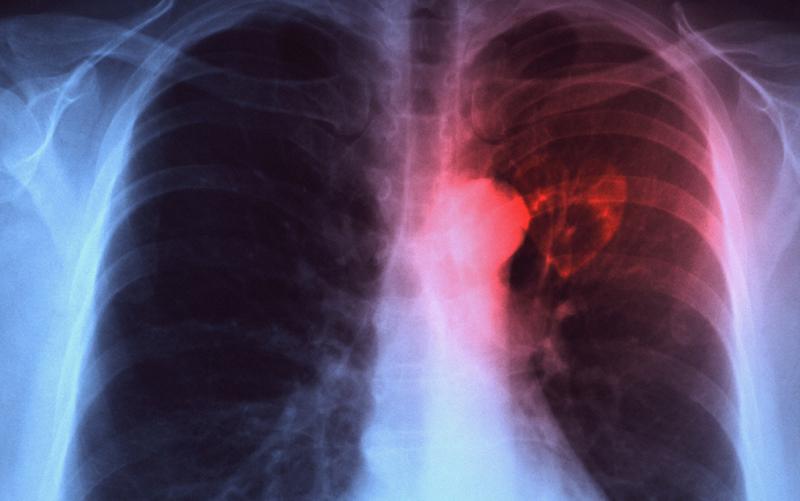

Реакцию гиперчувствительности могут провоцировать фенол, натрий хлор и консерванты, которые присутствуют в препарате для туберкулиновой пробы. Как правило, побочные эффекты развиваются у аллергиков. Таким людям обычно доктора предлагают альтернативные методы проверки инфицирования туберкулезом. Например, определить наличие палочки Коха можно при помощи пробы Суслова, рентгена грудной клетки либо анализа сыворотки на иммунограмму.